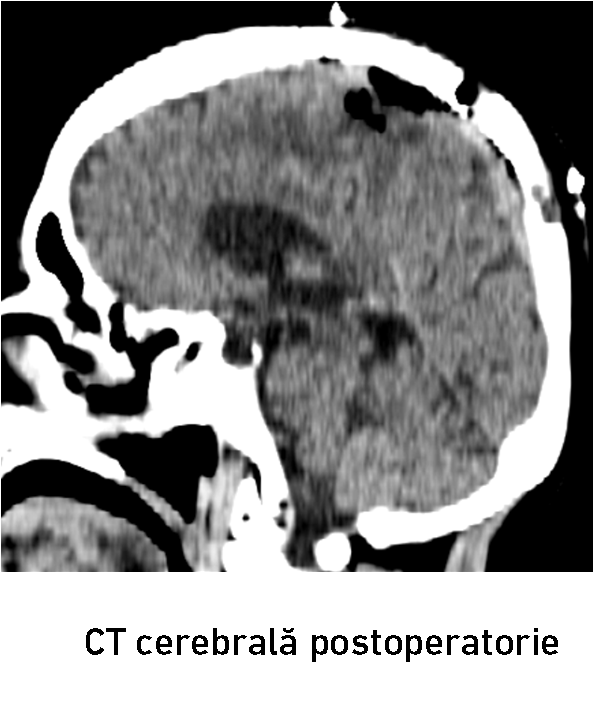

După 2 ore de la tratamentul endovascular, echipa chirurgicală a dat startul intervenției convenționale prin craniotomie osteoplastică. Grație embolizării preoperatorii, hemoragia intraoperatorie a fost redusă până la 500 ml. A fost realizată ablația totală macroscopică a meningiomului cu coagularea atașamentului dural, fapt confirmat prin CT cerebrală postoperatorie (fig. 8-10). Intervenția a fost efectuată de colaboratorii IMSP Spitalul Clinic Republican formată din conf. univ. d.ș.m. Eduard Eftodiev, dr. Alexandru Șumleanschi, dr. Iana Cotorcea, asistenta anestezistă Doina Dragan, asistentele de operație Maria Mutelică și Macela Cucheev. Toate obiectivele propuse au fost realizate cu succes de către echipa neurochirurgicală. Bolnava a fost externată la ziua 9-a postoperator în stare satisfăcătoare. Starea pacientei s-a ameliorat după tratamentul combinat : a regresat hemipareza în membrele drepte, pacienta devenind autonomă (Karnofsky PS 70%). Cu toate că bolnava a recuperat spectaculos forța în membrele hemicorpului drept, a fost recomandat continuarea tratamentului de recuperare şi neuroreabilitare.